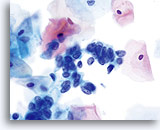

Abnorme Endometriumzellen (NOS)

(51-jährige Patientin, perimenopausal) Neben einzeln liegenden reifen Plattenepithelzellen findet sich ein kleiner, dreidimensionaler Drüsenzellverband. Das Zytoplasma weist multiple, gut erkennbare Vakuolen auf. Die Zellen haben sich abgerundet und die Kerne sind rund bis oval mit klarem Chromatinmuster.

40x

Biopsie – Benignes proliferierendes Endometrium

Abnorme Endometriumzellen (NOS)

(51-jährige Patientin, perimenopausal) Neben einzeln liegenden reifen Plattenepithelzellen findet sich ein kleiner, dreidimensionaler Drüsenzellverband. Das Zytoplasma weist multiple, gut erkennbare Vakuolen auf. Die Zellen haben sich abgerundet und die Kerne sind rund bis oval mit klarem Chromatinmuster.

40x

Biopsie -Benignes proliferierendes Endometrium